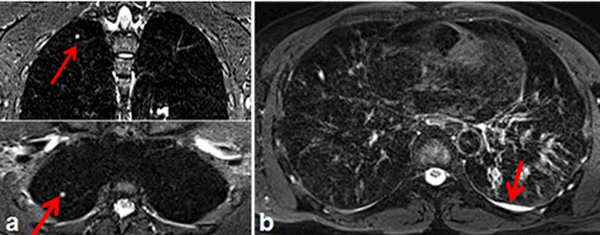

![Туберкулез на снимке МРТ]()

Туберкулез на снимке МРТ (стрелками показаны очаги в паренхиме легких (а) и туберкулезный плеврит (b))

- диссеминированная форма туберкулеза представлена множественными очагами, которые могут иметь разную форму, в том числе однородную правильную. На снимках МРТ наблюдают распространенность патологических признаков по всем отделам легких;